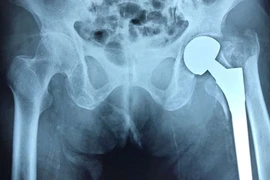

Thay khớp háng cho cụ bà 101 tuổi, gãy liên mấu chuyển xương đùi

Gãy liên mấu chuyển xương đùi chiếm tới 55% trong các loại gãy xương đầu trên xương đùi ở người cao tuổi. Bệnh gây nhiều biến chứng đe dọa tính mạng.

Gãy xương vùng khớp háng ở người cao tuổi: Chưa được quan tâm đúng mức?

(khoahocdoisong.vn) - Sức khoẻ và sự an toàn xương khớp ở người cao tuổi là một vấn đề y tế được quan tâm những năm gần đây, nhưng liệu đã đúng mức vấn đề sức khoẻ này chưa?